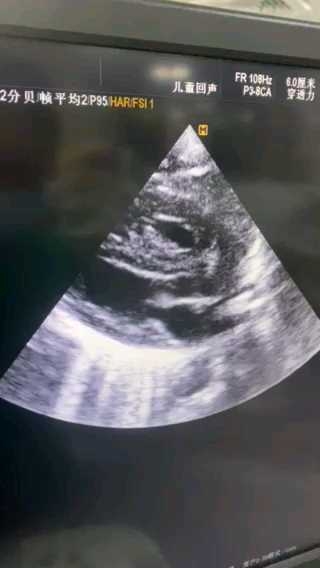

来自同行的“钟艳lin"的病例:足月,未产检,因胎儿窘迫剖宫术,有诊断窒息,气管插管有吸到胎粪,上机后血氧维持尚可。血压低,有生理盐水扩容2次,10ml/kg,心脏彩超提示室间隔肥厚,右心肥厚,左心充盈欠佳,左右心房不大,pda双向分流,无三尖瓣反流,卵圆孔1.6mm。扩容后下腔静脉4.2mm。

使用肾上腺素心率加快,后改用去甲肾上腺素,一天后,心脏彩超提示左心充盈有好转,右心肥厚仍存在,不存在SAM…

从慢放的镜头来看,前瓣靠拢室间隔发生在收缩后期或舒张早期,而不是收缩中期,此时左室已经排空,并不存在导致血排不出去,没有事实上左输出道梗阻表现。另一方面左室几乎排空也可以说明左室收缩功能良好或者亢进…。虽然没有输出道梗阻sam,但强心应该也没有任何意义,因为收缩时左心室几乎已经排空。经过去甲补液等治疗,左室充盈在好转!